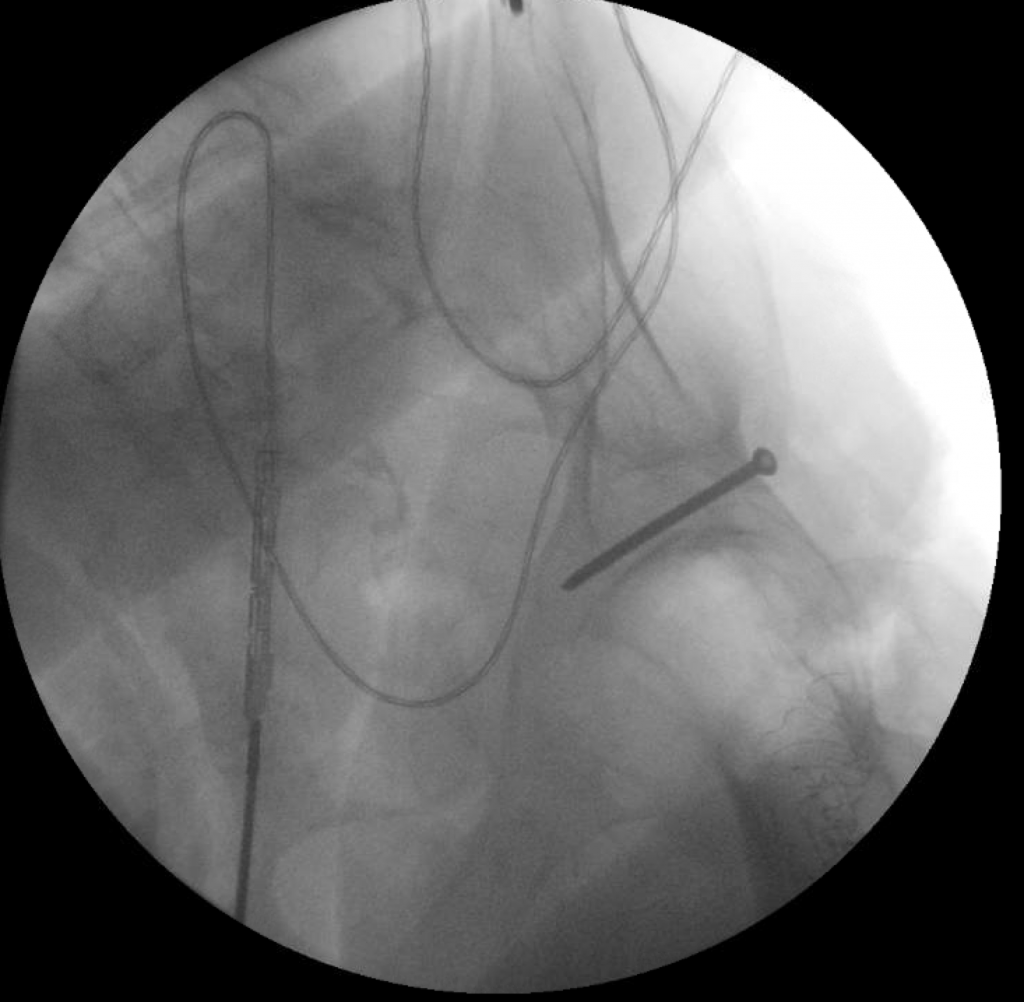

The patient underwent simultaneous acetabular ORIF and complex THA reconstruction by Dr. Darwin Chen and Dr. David Forsh (Chief of Orthopaedic Trauma). A Kocher-Langenbeck approach was used for exposure. The anterior and posterior columns were secured together using a single posterior-to-anterior screw just superior to the acetabulum. An acetabular shell was implanted with excellent inherent stability, followed by screw fixation into the superior dome as well as inferiorly into the ischium.

After a period of limited weight bearing, the patient was able to return to full function without deficits.